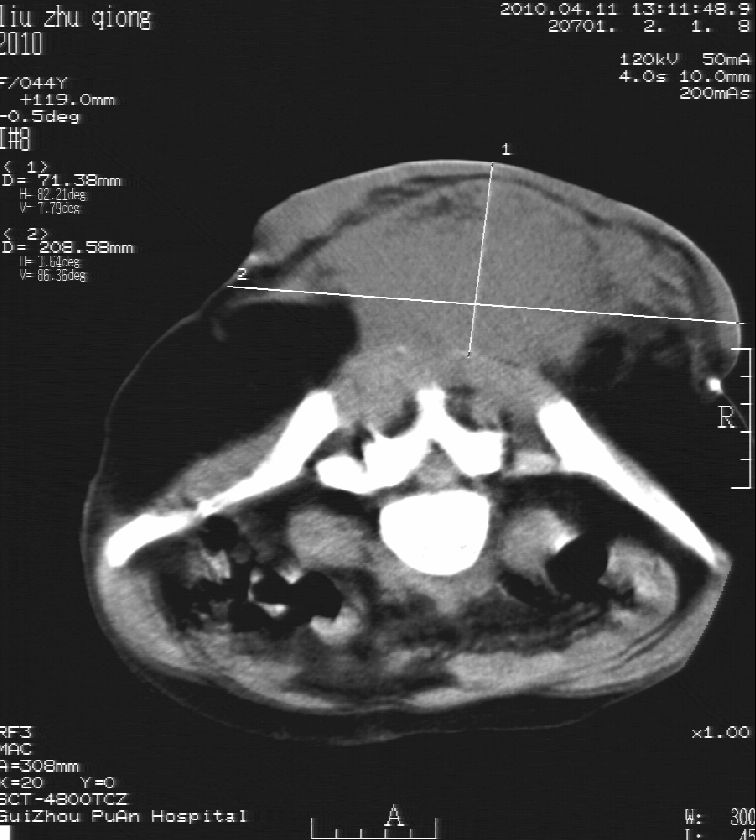

刘某,女,44岁,生第一胎时发现腰背部肿块,黄豆大小,至今17年,呈逐年增大,现行ct检查如下,敬请各位指点。

病史:女,44岁,腰背部肿块,黄豆大小,17年,呈逐年增大。

ct示:骶骨见软组织密度影,似见细条状,或花边状高密度影,考虑不典型钙化灶,向后生长,超出皮肤,可见骶骨破坏,第5幅ct图似与骶管相通。

病程长,生长慢,肿块巨大,考虑神经纤维瘤,脂肪密度可以用肿瘤生长过程中包裹入皮下脂肪解释。